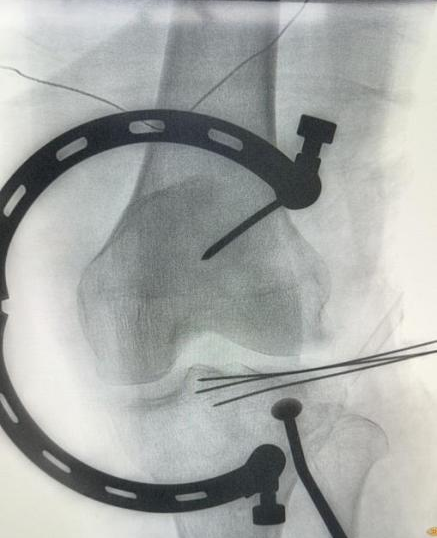

手术在 X 线透视导航下精准实施,团队仅于患者膝关节处作约 4 厘米小切口,借助特制撑开器充分暴露关节面,以顶棒精准复位塌陷软骨面,经细克氏针临时固定后,置入钢板,再通过 2 个仅 0.5 厘米的微型置钉孔完成螺钉固定。